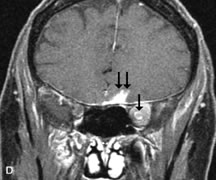

Lymphomas have MRI characteristics similar to those of inflammatory lesions in that they are hypointense to fat and isointense to muscle on T1-weighted images (Fig. 22). They may appear hyperintense to fat on T2-weighted images, perhaps owing to less fibrosis than that seen in orbital inflammatory pseudotumor, although this is not a consistent finding.31,50,66 Lymphoid tumors typically enhance moderately after contrast injection. Unfortunately, studies have shown that tumor density and homogeneity are similar between inflammatory and malignant orbital infiltrates, and MRI cannot differentiate these lesions.72,73

Fig. 22. A and B. T1- and (C) T2-weighted MR scans demonstrate a poorly defined multicompartmental mass enveloping the lateral rectus, superior rectus, and levator palpebrac superioris muscles. The lesion is isointense to brain on T1- and T2-weighted scans, as is typical for highly cellular neoplasms. D. Postcontrast fat-suppressed T1-weighted scan demonstrates intense enhancement of the infiltrating intraconal and extraconal tumor.